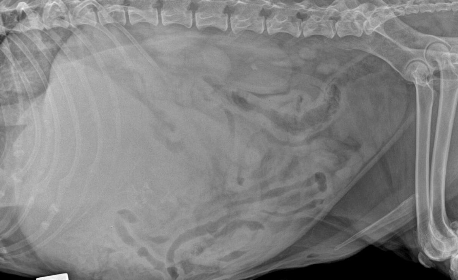

what will be seen on abdominal radiographs in patients with hemangiosarcoma?

nonspecific: mass

loss of serosal detail